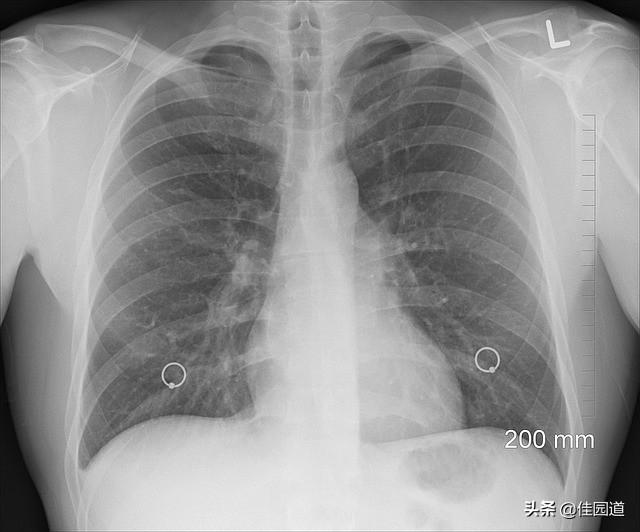

学校の先生たちは、この病気は教科書通りにはならないことを繰り返し強調していた!新型コロナウイルス肺炎に感染したすべての患者が典型的な症状を示すわけではないので、医師が診断を下すのは難しくなる。疫学(湖北省武漢市での居住歴、武漢市出身者との接触歴など)、臨床症状(発熱、咳、倦怠感など)、関連する補助検査(定期的な血液検査、胸部X線検査など)を考慮し、新型コロナウイルス肺炎の疑いが強ければ、専門家とのディスカッションを経て、最終的に新型コロナウイルス肺炎と診断します。診断を確定するために、呼吸器検体または血液検体をリアルタイム蛍光RT-PCR法で新型コロナウイルス核酸陽性とする。疑われる症例が呼吸器病原体核酸検査で2回連続して陰性(検体間隔が少なくとも1日以上)であれば、除外できる。

新型コロナウイルス感染による肺炎の管理プロトコールによると、新型コロナウイルス肺炎の主な症状は、発熱、乾いた咳、倦怠感であり、少数の患者では鼻づまり、鼻水、咽頭痛、下痢である。最近発表された2つの論文でも触れられているように、新型コロナウイルス感染患者における最も一般的な症状は発熱と倦怠感である。感染が確認された41例のデータでは、確認された集団のほぼ全員(98%)が発熱、76%が咳、44%が筋肉痛・倦怠感を訴えた。99例の症例分析によると、83%に発熱、82%に咳、31%に息切れ、少数ながら頭痛、咽頭痛、鼻水、胸痛、下痢があり、90%以上の症例で上記の症状の少なくとも1つが見られた。血球数ではリンパ球減少がよくみられ、胸部CT検査では全例で、地中ガラスの混濁、複数の肺分節または複数の肺葉の集積など、実質的な肺の異常が認められた。しかし、新型コロナウイルス感染症患者の中には、発熱がなく平熱の患者もいることも事実であるが、これはやはり少数派である。

現在の医療状況では、胸部X線検査と核酸検査で診断するのがベストだが、医師も検査機器も限られており、検査が必要な人があまりにも多いため、全員が胸部X線検査で核酸検査を受けると、多くの本当の患者が治療のチャンスを失ってしまうからだ。その上、フィルムを撮るために全員を病院に引っ張り出すのは非現実的だし、体温検査はふるいにかけるようなもので、たとえ感染者の80%を選別できたとしても、今はその割合がもっと高いかもしれない。

胸部X線写真では、初期には小さな斑状の影が多数認められ、進行すると両肺に多発性の浸潤影や多発性の地硝子影が認められるようになり、重症例では両肺に重度の固形変化が認められ、お馴染みの白い肺として現れることがある。

以上のことから、体温はあくまでも予備的なスクリーニングであり、体温測定、疑わしい人の体調や接触歴の聴取に加え、患者の他の症状、さらに血液検査、胸部レントゲン写真や胸部CT検査、必要に応じて核酸検査などを通じてもスクリーニングが可能であり、スクリーニング方法という観点からは、やはり体温測定と問診が最も簡便で効果的かつ迅速な方法であることがわかる。